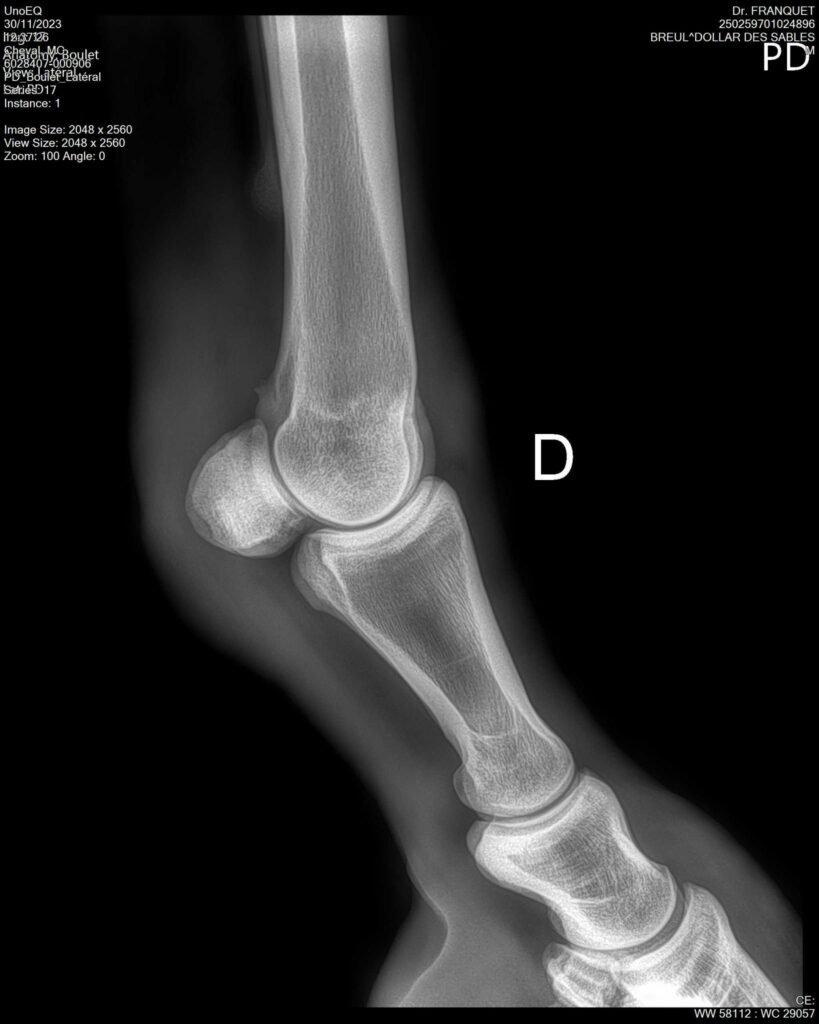

DOLLAR DES SABLES, Selle Français, hongre, 12 ans par DOLLAR DE MURIER x ABKE (ACORADO). Classé 135 avec professionnel à fait 125 avec amateur, récemment classé sur amateur 1GP 120. Très beau modèle ! Gentil cheval, respectueux avec des moyens et du sang. Transport OK, maréchalerie OK, santé RAS, Bilan clichés radios OK.

RADIOS